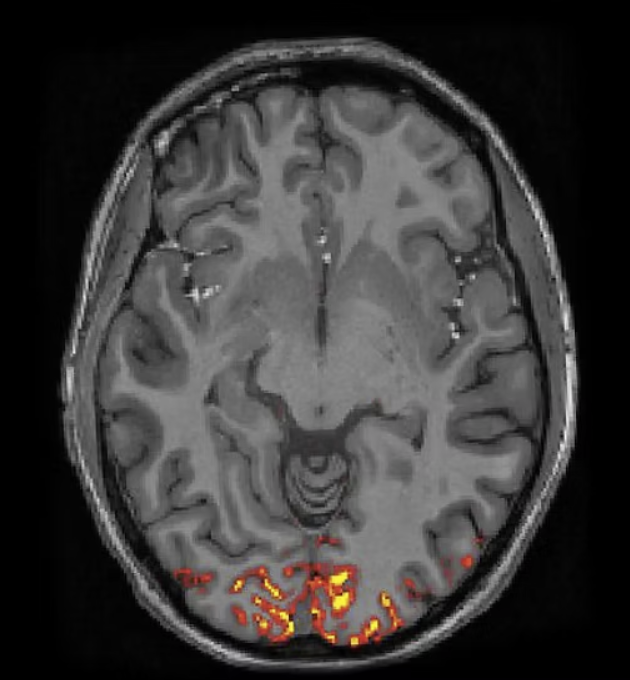

Attentional failures after sleep deprivation are locked to joint neurovascular, pupil, and cerebrospinal fluid flow dynamics.

Zinong Yang, Stephanie D. Williams, Ewa Beldzik, Stephanie Anakwe, Emilia Schimmelpfennig, and Laura D. Lewis.

Nature Neuroscience, 2025